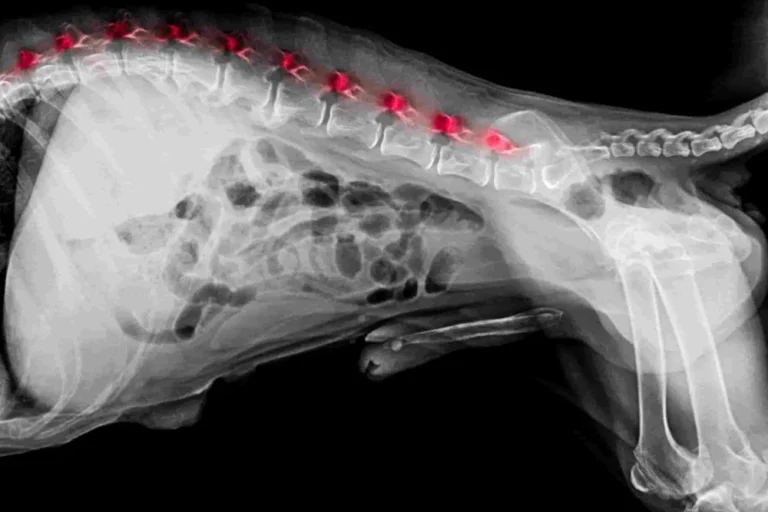

Spondylose beim Hund: Wenn der Rücken steif wird – Diagnose, Hausmittel & Therapie

Merkst du, dass dein Hund morgens schwerer aufsteht oder zögert, ins Auto zu steigen? Solche Veränderungen werden oft einfach auf das Alter geschoben. Doch häufig…